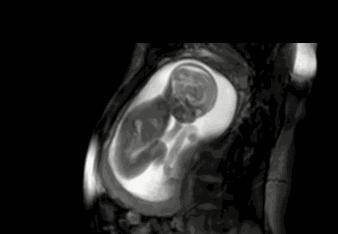

胎宝宝在宫腔内里的运动撞击到宫壁的小动作即为胎动,宝宝胎动受孕妈身体的敏感度、体型,宫内羊水数量,有没有怀过宝宝等影响,因此每位孕妈身体的感受都是不一样的。

宝宝胎动有的时候是整个胎宝宝连续性的翻滚运动,可以达到10多秒的时间。